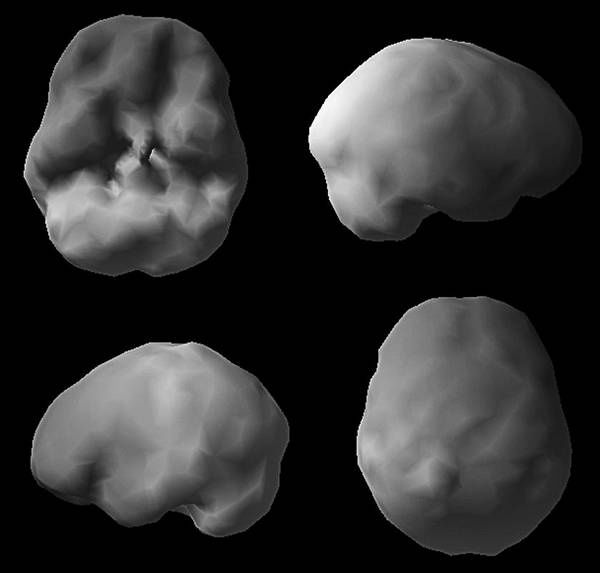

Больше узнать о состоянии здоровья своего мозга и риске развития болезни Альцгеймера поможет томограмма ОЭКТ. Когда мне исполнилось 50, мой лечащий врач назначил плановую колоноскопию. «А почему вы не хотите проверить мой мозг, – поинтересовался я, – разве другой конец туловища не столь важен?» Как узнать, что происходит в мозге, если не обследовать его? Я верю, что томограф в ближайшем будущем станет таким же привычным инструментом диагностики, как маммограф или колоноскоп. Он принесет особую пользу людям из группы риска и тем, у кого уже появились «ранние» симптомы. Поскольку большинство врачей еще не привыкли к томографии, многие пациенты узнают о своих проблемах «в голове», когда уже слишком поздно. А ведь на раннем этапе эти заболевания можно корректировать. Вот пример. Эд Эду семьдесят два, его дочь Кэндис привезла его к нам на прием из Ванкувера, Британская Колумбия. Кэндис была встревожена забывчивостью отца. Его настроение было хуже обычного, а суждения не столь хороши, как прежде. Некоторые финансовые счета он оплачивал дважды, а о других мог забыть. Когда она отвела его к местному невропатологу, тот диагностировал болезнь Альцгеймера, не сделав томограмму его мозга. Кэндис прочитала мою книгу «Измените свой мозг – и жизнь изменится» и расстроилась, что врач не сделал томограмму. Скан мозга Эда (горизонтальные срезы мозга показаны по направлению сверху вниз) ![]() См. срезы 15 и 16 и увидите «лобстера» Скан нормального мозга ![]() Полная, равномерная, симметричная активность Скан ОЭКТ мозга Эда ![]() Нетипичная структура для болезни Альцгеймера, мы видим увеличенные желудочки («дыра» в середине) и маленький мозжечок (в основании) Врач ответил, что уверен в своем диагнозе и не нуждается в подтверждении. Меня такое отношение всегда неприятно удивляет. Недовольная поведением врача, Кэндис привезла Эда к нам. На скане мозга Эда было видно, что желудочки мозга (заполненные жидкостью полости) увеличены. Такой рисунок на томограмме я называю лобстером, потому что он похож на перевернутого омара. Еще у Эда был слишком маленький мозжечок. Томограмма Эда определенно не походила на типичную картину поражения, которую мы наблюдаем при болезни Альцгеймера (низкая активность височных и теменных долей). Зато картина, как у Эда, часто обнаруживается при заболевании под названием «гидроцефалия с нормальным давлением». При ней блокируется нормальный отток жидкости из желудочков мозга и количество жидкости в них постепенно возрастает. Одновременно могут проявляться такие симптомы, как недержание мочи и нарушение походки, хотя и не обязательно. Поскольку этих симптомов у Эда не было, его невролог даже не подумал о другом диагнозе. А состояние Эда продолжало ухудшаться. Увидев скан, я сразу назначил консультацию с нейрохирургом. Тот согласился с моим диагнозом и провел шунтирование мозга Эда. Память восстановилась в течение 3 недель. Как можно помочь, если не посмотреть на пострадавший орган? ШАГ 3. Сосредоточьтесь на уменьшении специфических факторов риска Итак, вы представляете, какие факторы риска существуют. Что с ними делать? Вот список факторов и действий. • Фактор риска: Член семьи с болезнью Альцгеймера или схожим нарушением, либо у вас есть ген APO e4. • Действие: Проведите ранний скрининг и со всей серьезностью как можно раньше займитесь профилактикой. Реализуйте все описанные в этой книге стратегии прямо сейчас. • Фактор риска: Единичная черепно-мозговая травма или несколько черепно-мозговых травм. • Действие: Предотвращайте повторные черепно-мозговые травмы, как можно скорее реализуйте стратегии профилактики. • Фактор риска: Алкоголизм, наркотическая зависимость или курение в прошлом либо настоящем. • Действие: Остановите лечение и ищите скрытые причины, как можно раньше начинайте стратегии профилактики. • Фактор риска: Тяжелая депрессия или СДВ(Г), диагностированные врачом в прошлом или настоящем. • Действие: Лечитесь, занимайтесь профилактикой. • Фактор риска: Инсульт, болезнь сердца, высокий уровень холестерина, артериальная гипертензия, диабет, история лечения рака, эпилептические припадки в прошлом или настоящем. • Действие: Лечение и стратегии профилактики. • Фактор риска: Ограниченная физическая нагрузка (меньше двух получасовых тренировок в неделю). • Действие: тренируйтесь три раза в неделю или больше. • Фактор риска: Образование ниже среднего школьного или работа, не требующая периодического освоения новой информации. • Действие: Учитесь всю жизнь, непрерывно. • Фактор риска: Сонное апноэ. • Действие: Пройдите осмотр и займитесь лечением апноэ. • Фактор риска: Дефицит эстрогена или тестостерона. • Действие: Подумайте о гормонозаместительной терапии. Думаю, вы поняли принцип. Устраните факторы риска, которые поддаются уменьшению, и работайте над долгосрочным здоровьем мозга. ШАГ 4. Поддерживайте активность тела и мозга В следующих главах вы увидите, что физические и умственные тренировки – это лучший способ сохранить молодость мозга. Тренировка ума помогает мозгу укрепить имеющиеся синаптические связи и создавать новые. Больше об интеллектуальных тренировках вы узнаете в главе 5. Физические упражнения повышают приток крови к мозгу, улучшают его обеспечение кислородом и помогают защитить мозг от вредных молекул, таких как свободные радикалы. Подробнее о физических упражнениях будет рассказано в главе 3. ШАГ 5. Принимайте пищевые добавки для поддержания здоровой функции мозга О пищевых добавках накоплено много информации, а также дезинформации. Отделить истину от заблуждений очень важно, потому что некоторые добавки действительно работают. Каждый день принимайте поливитамины и рыбий жир. Проверьте свои показатели витамина D и при необходимости оптимизируйте их. Вот еще несколько доказавших свою эффективность добавок. • Рыбий жир и куркумин для уменьшения воспалений. • N-ацетилцистеин и альфа-липоевая кислота – чтобы повысить сопротивляемость тела свободным радикалам и окислительному стрессу. |